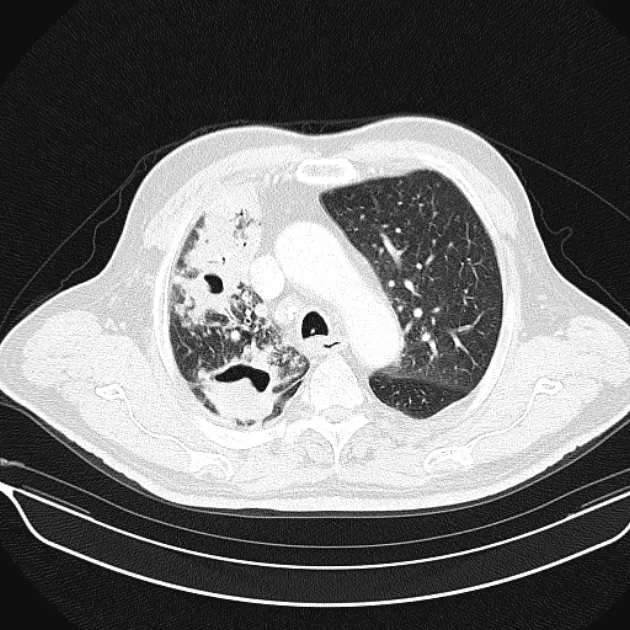

Post-primary pulmonary tuberculosis

대부분의 환자는 다음 두 곳에 생김

Posterior segments of the upper lobe

superior segments of the lower lobe

Typical findnigs

1) Patcy consolidation 또는 poorly defined linear and nodular opacities

2) air-fluid level : airway와 communication 형성 의미

3) endobronchial spread